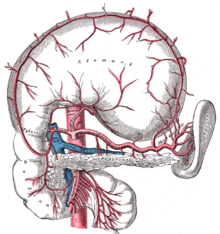

Die Versorgung der Bauchspeicheldrüse erfolgt über drei größere Gefäße: Die obere Bauchspeicheldrüsen-Zwölffingerdarmarterie (Arteria pancreaticoduodenalis superior), die große Bauchspeicheldrüsenarterie (Arteria pancreatica magna) und die untere Bauchspeicheldrüsen-Zwölffingerdarmarterie (Arteria pancreaticoduodenalis inferior) verzweigen sich in weitere kleinere Arterien, die zum Teil miteinander in Verbindung treten (anastomosieren).[5]

Das venöse Blut aus Körper und Schwanz der Bauchspeicheldrüse wird von kleinen Bauchspeicheldrüsenvenen (Venae pancreaticae) über die Milzvene (Vena splenica) in die Pfortader (Vena portae) geleitet. Das Blut aus dem Kopf der Bauchspeicheldrüse gelangt über die Bauchspeicheldrüsen-Zwölffingerdarm-Vene (Vena pancreaticoduodenalis) in die obere Gekrösevene (Vena mesenterica superior) und dann ebenfalls in die Pfortader.[6]